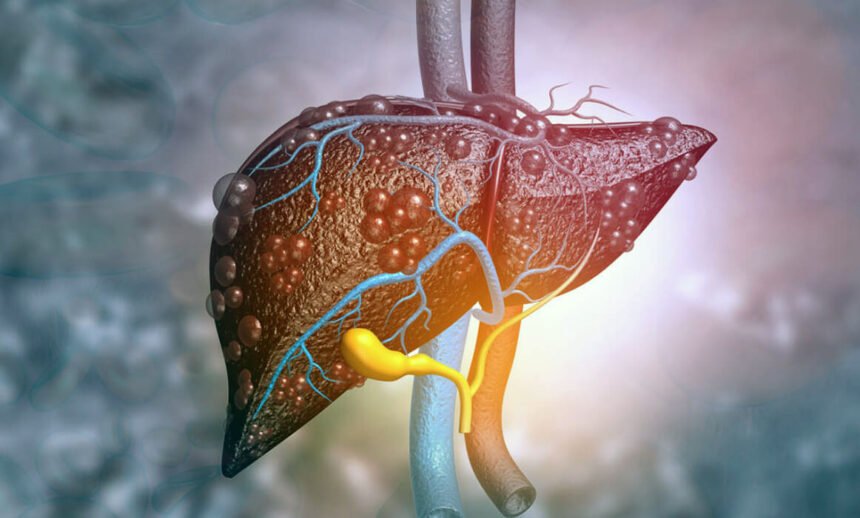

Цироз печінки – це серйозне захворювання, при якому печінка зазнає незворотних змін і втрати функцій. Це прогресивне захворювання, яке виникає, коли здорові клітини печінки заміщуються рубцевою тканиною. Цей процес поступово порушує нормальну роботу печінки, що може призвести до важких наслідків для організму.

Цироз може бути викликаний різними факторами, і його розвиток є досить тривалим. Зазвичай люди не помічають симптоми на ранніх стадіях, і лише на пізніших етапах захворювання виявляються очевидні ознаки порушення роботи органу.